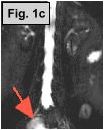

Fig. 1a-c: MRI of the L-spine (sagittal T2 weighted, coronal scout, and coronal MR Myelogram, respectively) demonstrates an incidental 4-5 cm cystic-appearing mass in the right pelvis on limited views of the pelvis. Fig. 2: a helical CT image of the pelvis, revealing a 4x5 cm low-density mass in the right hemipelvis to the right of the uterus. Fig. 3: Pelvic ultrasound shows a moderately enlarged right adnexa measuring 5 cm with low-level echoes.

IMAGING FINDINGS:  Fig. 1a-c show MRI images of the L-spine (sagittal T2 weighted, coronal scout, and coronal MR Myelogram, respectively).  They demonstrate mild scattered disc bulges and an incidental 4-5 cm cystic-appearing mass in the right pelvis on limited views of the pelvis. Incidentally, the MR Myelogram (Fig. 1c) also nicely shows the thecal sac and renal collecting systems.  Fig. 2 shows a helical CT image of the pelvis, revealing a 4x5 cm low-density mass in the right hemipelvis to the right of the uterus with CT density of about 20 Hounsfield units on pre- and post-contrast images.  A repeat transabdominal and endovaginal pelvic ultrasound with Doppler performed at AIC (Fig. 3) showed a moderately enlarged right adnexa measuring 5 cm with low-level echoes.